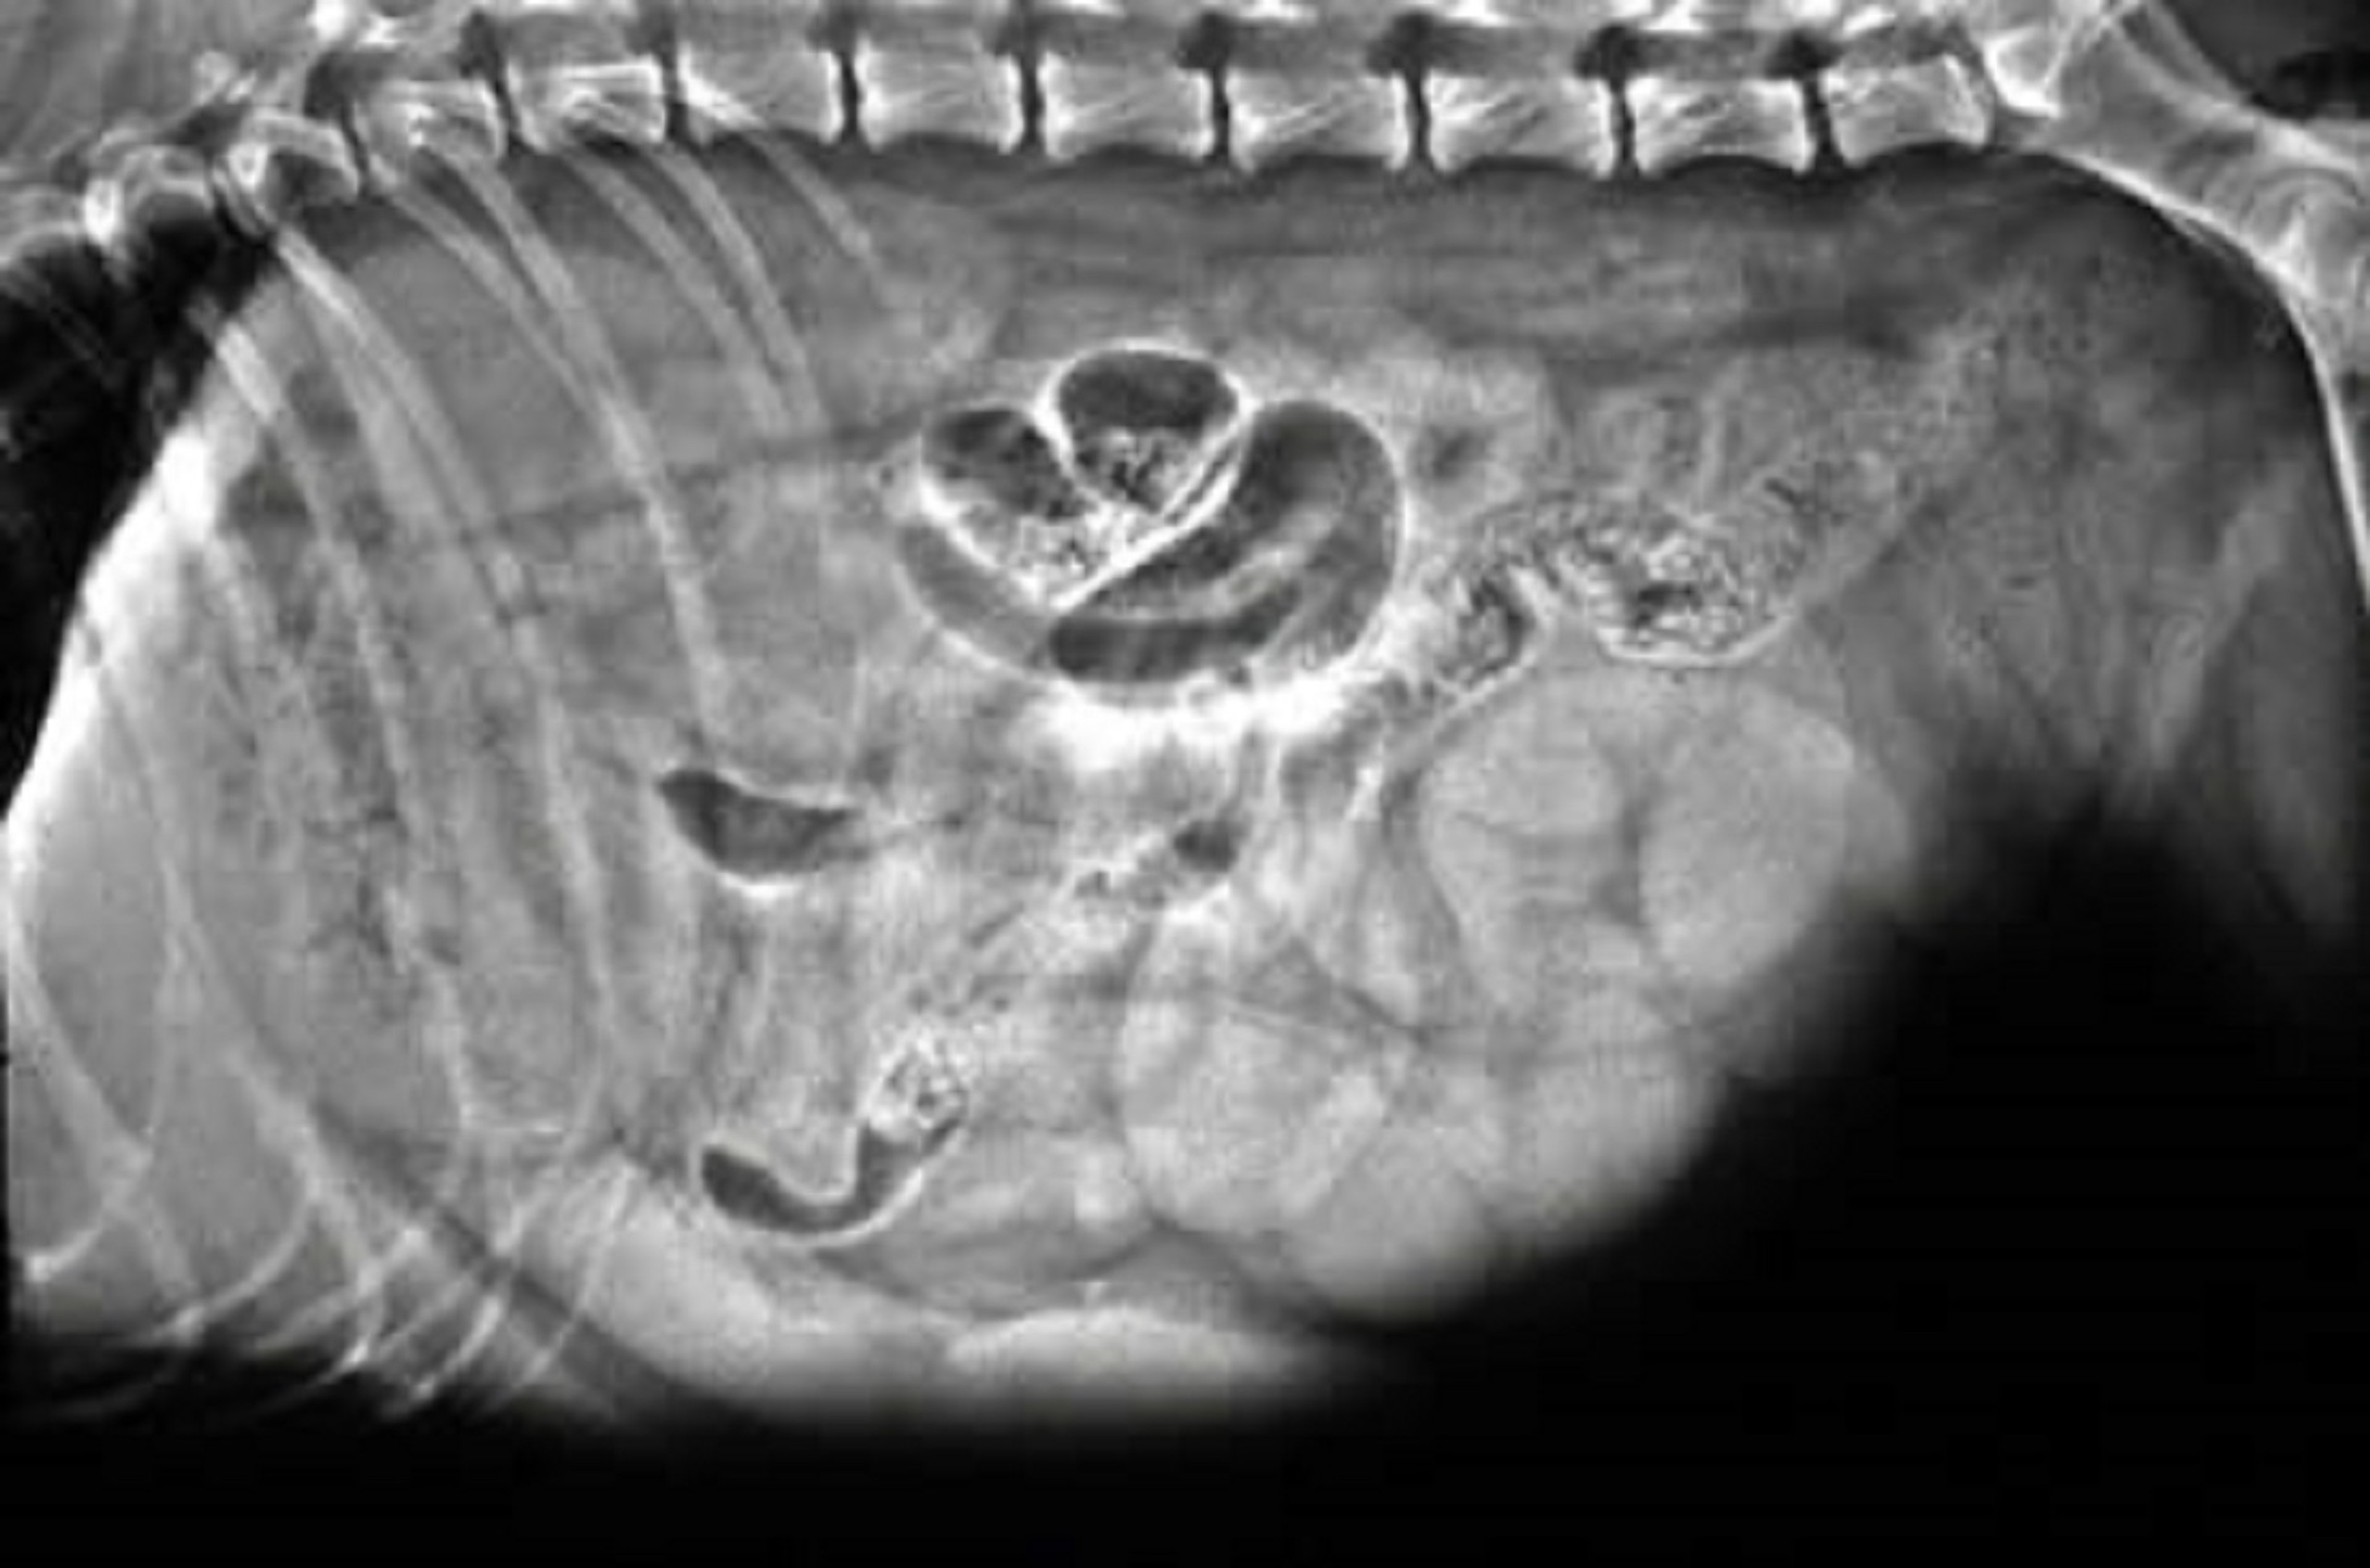

Pyometra, dog (radiograph)

Lateral abdominal radiographic view of a 10-year-old Norwegian Elkhound with pyometra. Observe the fluid-filled tubular organ located between the descending colon and the urinary bladder.

Courtesy of Dr. Ronald Green.